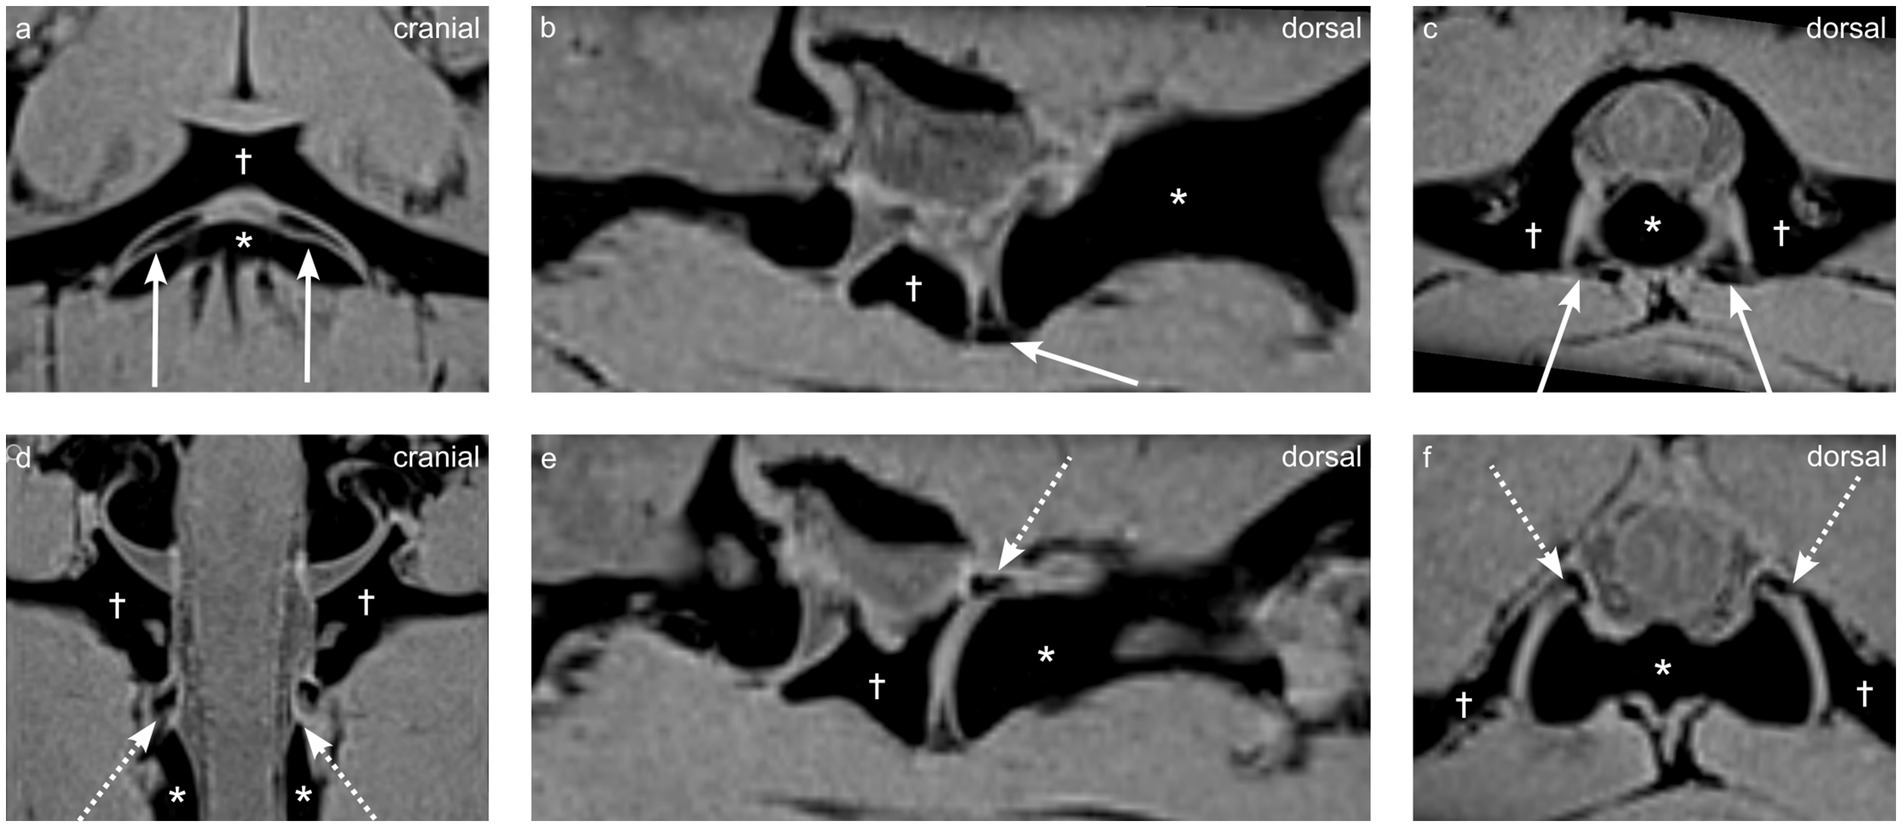

Purpose Synovial folds of the lateral atlantoaxial joints are well described normal anatomical structures in humans, which play a potential role in neck pain; however, scant information exists regarding these structures in dogs. The purpose of this study was to identify and describe atlantoaxial synovial folds in dogs using magnetic resonance imaging (MRI), gross anatomy and histological examination. Methods Six client-owned dogs, euthanized for reasons unrelated to this study and without known disease in the craniocervical region, underwent postmortem MRI of the cranial cervical spine (3 Tesla, Siemens Magnetom Vida) using T2-weighted (T2w), T1-weighted (T1w), short tau inversion recovery (STIR), Dixon, and fat-suppressed volumetric interpolated breath-hold examination (VIBE) sequences. In five dogs the lateral atlantoaxial joints were gross anatomically dissected, while one of them underwent histological examination. Results Fat-suppressed VIBE sequences provided optimal visualization of synovial folds within the atlantoaxial joints. Ventral synovial folds were discernible in all dogs by MRI and gross anatomical examination presenting as ventral synovial bulges extending into the joint space. While smaller dorsal synovial folds were identified by MRI only in 2 dogs, but by gross anatomical examination in all dogs. Light microscopy of the histological specimen confirmed that the folds were extensions of the joint capsule`s synovial membrane, which were mainly composed of vascularized connective and adipose tissue; and were covered by synovial cells. Discussion/Conclusion Synovial folds are present in canine atlantoaxial joints free from known atlantoaxial disease. Dorsal and ventral folds could be visualized on post-mortem macroscopic and histological examinations. The larger ventral folds were consistently visualized using MRI with fat-suppressed VIBE sequences. The anatomical structure of the canine synovial folds suggests a similarity to humans, indicating that some conditions may analogously affect the synovial folds. Further investigations are warranted to elucidate the clinical relevance of these synovial folds in dogs.